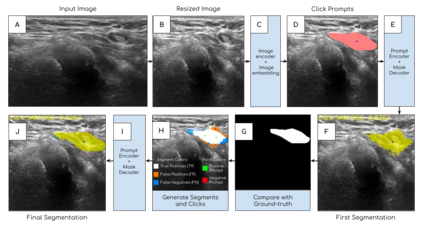

The newly released Segment Anything Model (SAM) is a popular tool used in image processing due to its superior segmentation accuracy, variety of input prompts, training capabilities, and efficient model design. However, its current model is trained on a diverse dataset not tailored to medical images, particularly ultrasound images. Ultrasound images tend to have a lot of noise, making it difficult to segment out important structures. In this project, we developed ClickSAM, which fine-tunes the Segment Anything Model using click prompts for ultrasound images. ClickSAM has two stages of training: the first stage is trained on single-click prompts centered in the ground-truth contours, and the second stage focuses on improving the model performance through additional positive and negative click prompts. By comparing the first stage predictions to the ground-truth masks, true positive, false positive, and false negative segments are calculated. Positive clicks are generated using the true positive and false negative segments, and negative clicks are generated using the false positive segments. The Centroidal Voronoi Tessellation algorithm is then employed to collect positive and negative click prompts in each segment that are used to enhance the model performance during the second stage of training. With click-train methods, ClickSAM exhibits superior performance compared to other existing models for ultrasound image segmentation.